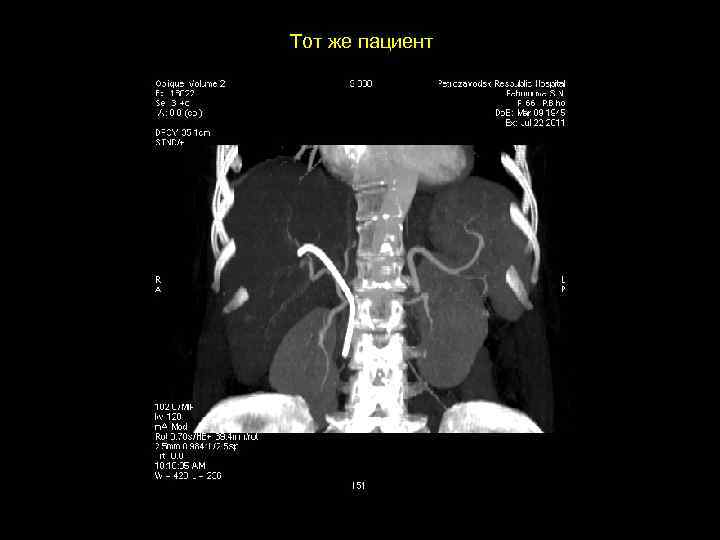

Тот же пациент